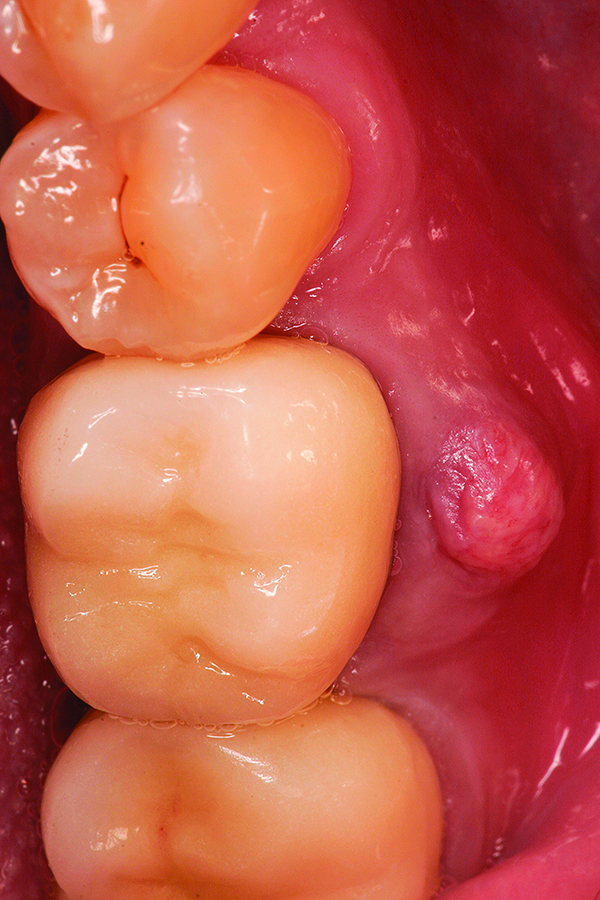

Fig 6. Placement of dental implants into healed bone. Note complete circumferential bone surrounding all aspects of the dental implants.

Figure 6

Fig 13. Placement of dental implant into healed bone. Note complete circumferential bone surrounding all aspects of the dental implant.

Figure 13

Fig 18. Surgical site at 3 months healing.

Figure 18